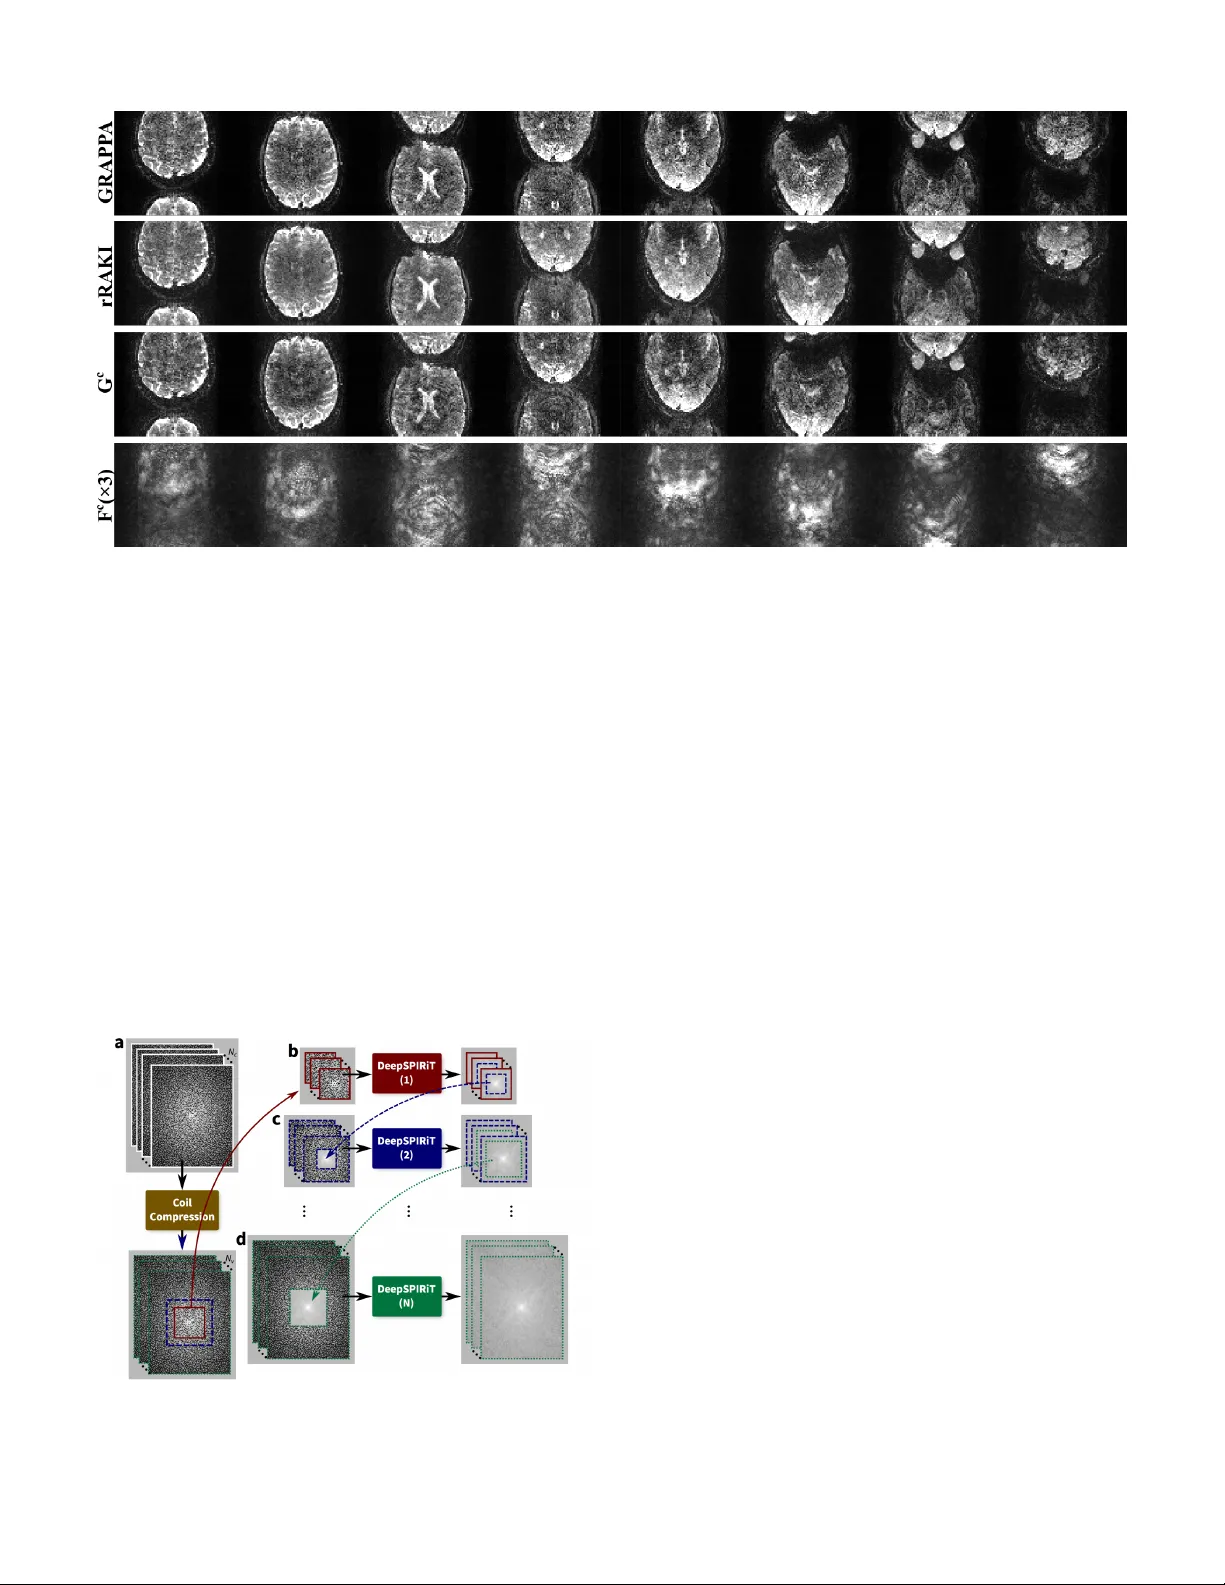

이 논문은 병렬 MRI 가속을 위한 딥러닝 기반 재구성 방법들을 포괄적으로 정리한다. 서론에서는 MRI가 다른 영상 modality에 비해 본질적으로 느린 데이터 획득 속도를 가지고 있어, 스캔 시간 단축이 임상적 중요 과제임을 강조한다. 병렬 영상(parallel imaging)은 다중 코일 배열을 이용해 공간 인코딩을 보강함으로써, 기존 SENSE, GRAPPA, SPIRiT 등 다양한 전통적 방법을 탄생시켰다. 첫 번째 섹션에서는 다중 코일 신호 모델을 수식으로 제시하고, 이미지 도메인과 k‑space 도메인에서의 전통적 병렬 영상 흐름을 도식화한다. 이미지 도메인에서는 SENSE가 코일 감도 맵을 사전 계산하고, 역푸리에 변환 후 별칭을 제거하는 과정을 거친다. 이때 CG‑SENSE와 같은 반복 최적화가 필요하며, 잡음 억제를 위해 조기 종료(early stopping)나 정규화 항을 추가한다. k‑space 도메인에서는 GRAPPA가 선형 이동 불변 커널을 학습해 누락된 라인을 보간한다. SPIRiT은 자기 일관성(self‑consistency) 원리를 도입해, 모든 코일의 k‑space 데이터를 동시에 고려하는 선형 커널을 사용한다. 두 번째 섹션에서는 비선형 정규화와 압축 센싱(compressed sensing) 기법을 소개한다. ℓ₁ 기반 스파스 정규화, Total Variation, Wavelet 변환 등은 무작위 샘플링과 결합해 별칭을 무작위 잡음처럼 만들고, 이를 최적화 문제(데이터 피델리티 + 정규화)로 풀어 재구성한다. Total Generalized Variation(TGV)와 같은 고차 정규화는 이미지 경계 보존에 유리하며, 저차원 저랭크 모델은 동적 MRI에 적용된다. 핵심은 딥러닝을 이용한 정규화와 보간의 최신 연구이다. 이미지 도메인에서는 U‑Net, Residual Dense Net, GAN 등을 활용해, 전통적 ℓ₁ 정규화 대신 학습된 비선형 사전(prior)을 적용한다. 이러한 네트워크는 데이터 일관성 항을 손실 함수에 포함시켜, 물리적 제약을 위배하지 않으면서도 높은 재구성 품질을 달성한다. k‑space 도메인에서는 복소수 CNN, K‑space U‑Net, 그리고 변분 베이즈 프레임워크와 결합된 딥러닝 보간기가 제안된다. 이들은 GRAPPA의 선형 커널을 대체하거나 확장해, 코일 간 상관관계와 비선형 패턴을 효과적으로 학습한다. 또한, 자기 일관성 제약을 손실에 포함시켜 SPIRiT과 유사한 안정성을 제공한다. 데이터와 벤치마크에 관한 섹션에서는 현재 공개된 대규모 MRI 데이터셋(예: NYU FastMRI, Stanford MRI)와 그 한계를 논한다. 코일 감도 맵, A‑CS 영역, 다양한 가속 인자·샘플링 패턴을 포함한 메타데이터가 부족해, 연구 재현성과 일반화 평가에 제약이 있다. 저자는 향후 표준화된 데이터베이스 구축과, 공개된 코드·모델을 통한 공동 연구 환경 조성을 촉구한다. 마지막으로 남아있는 과제로는 (1) 멀티코일·멀티채널 데이터를 효율적으로 처리하는 경량 딥러닝 모델 설계, (2) 실시간 재구성을 위한 하드웨어 가속(예: FPGA, ASIC)과의 통합, (3) 다양한 임상 프로토콜에 대한 일반화와 도메인 적응, (4) 정규화와 데이터 일관성 사이의 최적 균형을 찾는 이론적 분석이 있다. 논문은 이러한 과제들을 정리하며, 딥러닝 기반 병렬 MRI 재구성이 임상 현장에 보편화되기 위해서는 알고리즘·데이터·인프라가 동시에 발전해야 함을 강조한다.